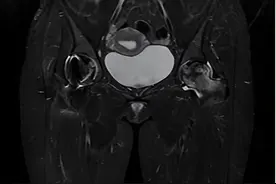

股骨头坏死(Avascular Necrosis of the Femoral Head,AVN)是一种股骨头因血液供应中断导致骨组织死亡的疾病,是骨坏死大类中的一种比较常见的病症。早期症状包括髋部隐痛、活动受限,后期可能引发股骨头塌陷、骨关节炎甚至残疾。